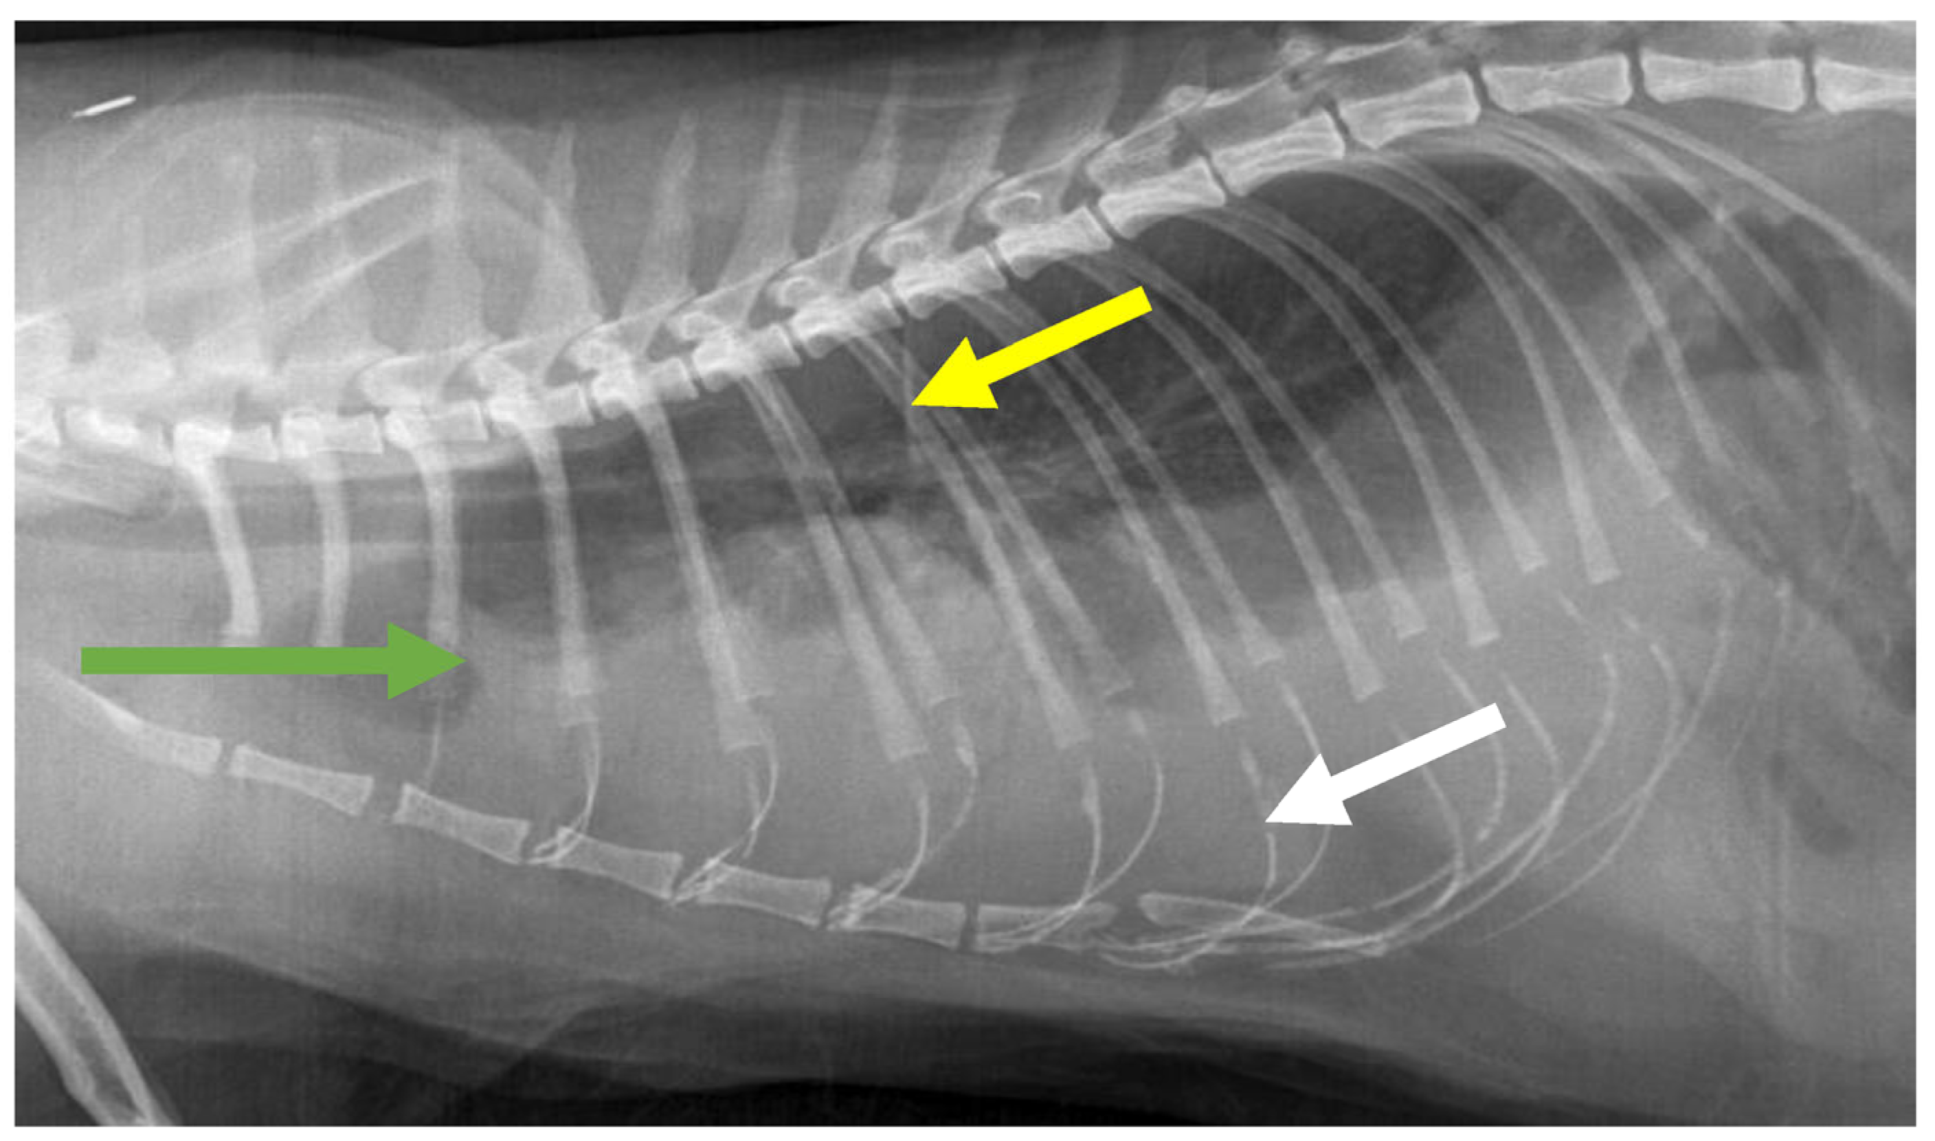

7.4. Diagnostic Imaging in FIP

7.4.1. Routine Imaging: Ultrasonographic and Radiographic Findings

| Summary of Section 7: Diagnosis of FIP; Section 7.4: Diagnostic imaging in FIP: No specific ultrasonographic or radiographic findings exist for FIP. Ultrasonography (in particular) and radiography can show the presence of effusions. Pneumonia due to FIP that is occasionally reported can be associated with radiographic changes. Ultrasonography can reveal abdominal lymphadenomegaly or lymphadenopathy and/or abnormalities of the liver, spleen, intestines and/or kidneys (which can include a medullary rim sign), depending on which organs are affected. Imaging can also be of use to the direct sampling of abnormal tissues, e.g., fine-needle aspirate for cytology examination to reveal non-septic pyogranulomatous inflammation, or ultrasound-guided needle core (e.g., tru-cut) biopsies can be collected and submitted for histopathology. When a cat is showing neurological signs, the imaging of the brain by magnetic resonance imaging, if available, with contrast, can be useful to demonstrate neurological abnormalities (such as obstructive hydrocephalus, syringomyelia, foramen magnum herniation and marked contrast enhancement of the meninges, third ventricle, mesencephalic aqueduct, and brainstem). A description of computerised tomography findings in cats with neurological FIP has not been published, but MRI is likely to be more sensitive in the detection of subtle intraparenchymal lesions. Advanced imaging of the central nervous system is indicated before performing cerebrospinal fluid sampling to assess the potential risk of herniation. |